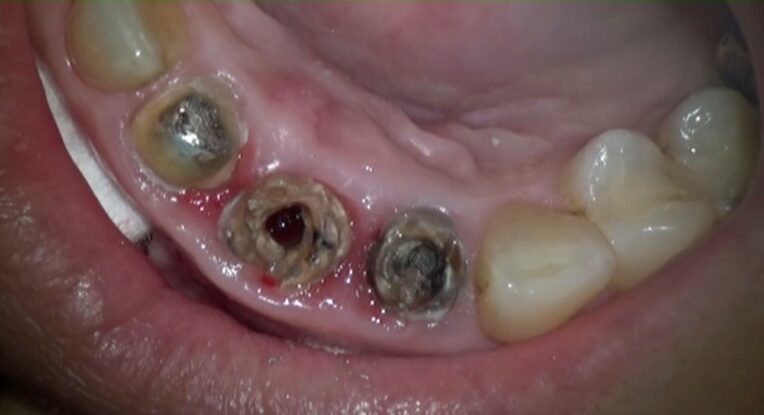

右上1番は、根尖部の破壊が非常に大きい。

炎症が短期間で起こったものではなく、

長期間にわたり感染が持続していたことを示す所見です。

一方、右上2番も問題を抱えていました。

根尖は開大しており、さらに

コア(土台)が頬側方向にずれて入っている。

これは、根管内を無菌的に管理するうえで、明らかに不利な構造です。